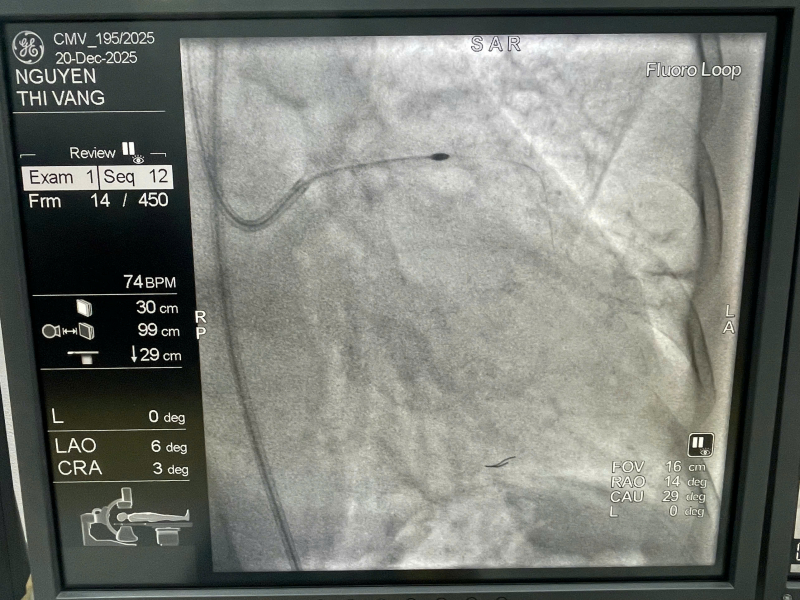

Ngày 20/12, tại TP Hồ Chí Minh, Bệnh viện 30-4 (Bộ Công an) đã triển khai thành công kỹ thuật khoan mảng xơ vữa mạch vành bằng hệ thống RotaPro cho một bệnh nhân nữ có tổn thương hẹp nặng lỗ xuất phát động mạch liên thất trước (LAD) kèm vôi hóa nặng dạng nốt (calcified nodule).

Trong trường hợp này, các y, bác sĩ đã sử dụng hệ thống khoan mảng xơ vữa thế hệ mới RotaPro, với mũi khoan kim cương quay tốc độ rất cao, nhằm bào mỏng và tái cấu trúc mảng vôi hóa, giúp lòng mạch trở nên mềm hơn, tạo điều kiện cho nong bóng và đặt stent tối ưu, an toàn. Quá trình can thiệp được hướng dẫn bằng siêu âm trong lòng mạch (IVUS), cho phép đánh giá chính xác mức độ vôi hóa, vị trí tổn thương và kết quả sau can thiệp. Thủ thuật diễn ra an toàn, kiểm soát tốt huyết động, không ghi nhận biến chứng, người bệnh ổn định sau can thiệp.